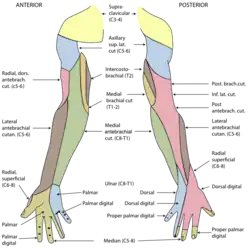

Sensory

The ulnar nerve also provides sensory innervation to the fifth digit and the medial half of the fourth digit, and the corresponding part of the palm:

- Palmar branch of ulnar nerve - supplies cutaneous innervation to the anterior skin and nails

- Dorsal cutaneous branch of ulnar nerve - supplies cutaneous innervation to the dorsal medial hand and the dorsum of the medial 1.5 fingers

- Sensory deficit: Loss of sensation or paresthesiae in ulnar half of the palm and dorsum of hand, and the medial 1½ digits on both palmar and dorsal aspects of the hand

- Sensory deficit: Loss of sensation or paresthesiae in ulnar half of the palm, and the medial 1½ digits on the palmar aspect of the hand, with dorsal sparing. The dorsal aspect of the hand is unaffected as the posterior cutaneous branch of the ulnar nerve is given off higher up in the forearm and does not reach the wrist.